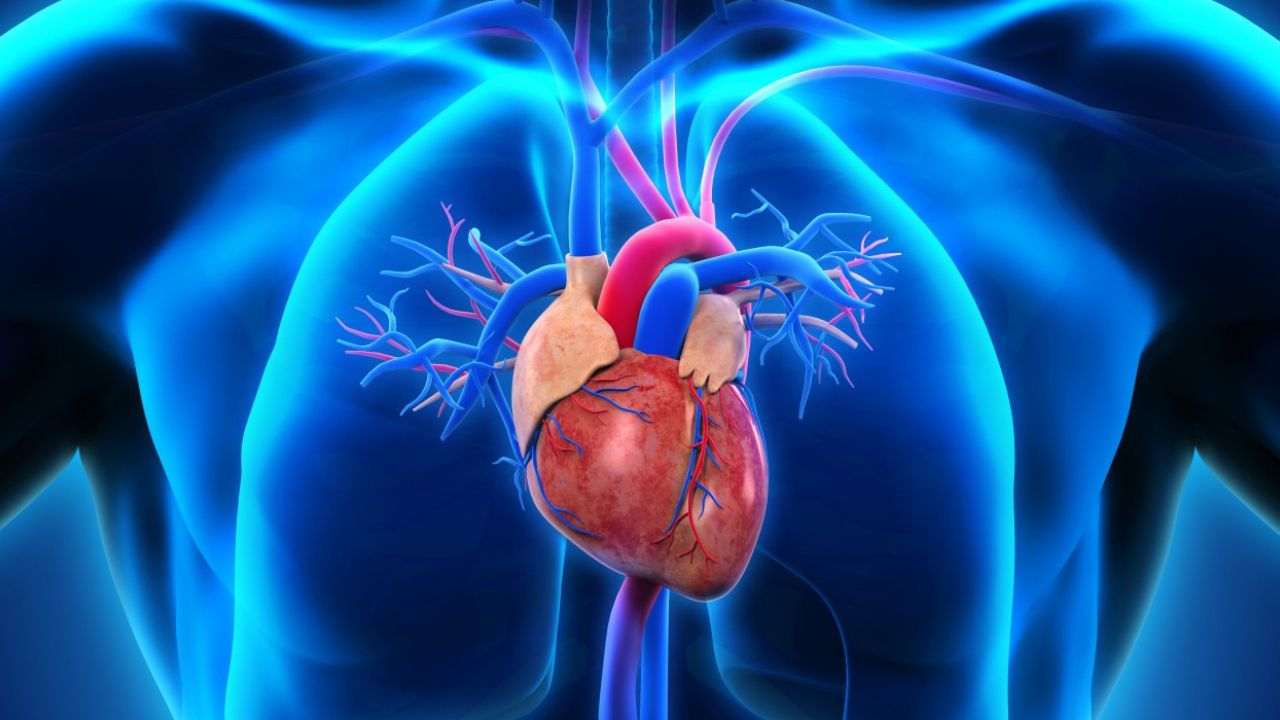

Numerous causes, some of which are beyond our control, contribute to the global problem of cardiovascular disease. We must, however, take extra precautions to protect our heart health over the holiday season.

In order to master our cardiac habits and prevent cardiovascular diseases during holiday season, we can do the following: